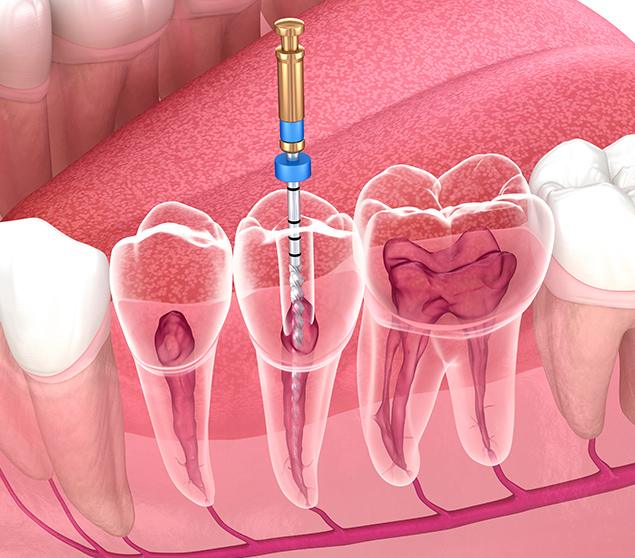

A diseased inner tooth can lead to pain, sensitivity, and the development of infection. In some cases, abscess formation may occur if infection progresses.

Following root canal therapy, a dental restoration is typically recommended to protect the treated tooth. A dental crown is often used to restore strength and reduce the risk of fracture. Your dentist will review restoration options and explain recommended next steps as part of your care.